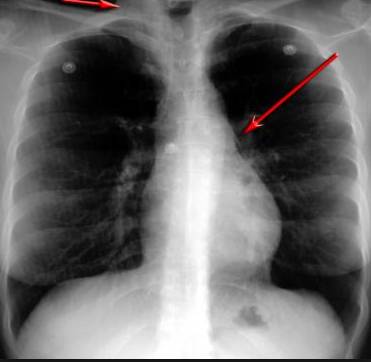

并且,因為呼吸系統(tǒng)結(jié)構(gòu)復(fù)雜,在體檢時醫(yī)生很難通過一種檢測手段,判定早期患者的病情。

所以,很多人發(fā)現(xiàn)自己得了肺病,哮喘或其他呼吸系統(tǒng)疾病的時候,已經(jīng)很危險了!多少人因此錯過最佳治療期!

可現(xiàn)在完全不一樣!

這臺4D掃描儀

能讓醫(yī)生有一雙可以透視的眼睛

把整個肺部看得清清楚楚!

使用這臺掃描儀,將直接把器官變成3D圖形!細(xì)微的毛細(xì)血管,幾毫米大的肺泡和支氣管,都將能看的一清二楚!

你的每一個氣泡,每一段支氣管,哪兒有病變都清清楚楚的將展示在醫(yī)生面前!

也就是說在一切都還沒開始惡化前,把這些有問題的器官組織都暴露的一清二楚:

沒有這項新技術(shù),醫(yī)生在做體檢的時候,很難通過一種測試斷定一個人是否有呼吸系統(tǒng)疾病。

可是現(xiàn)在他們不但能看到整個肺部的3維結(jié)構(gòu)圖。還能看到空氣進入人體后的所有微小變動!